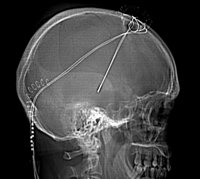

Los astrocitos utilizados en el estudio difieren de otros tipos de astrocitos presentes en el cerebro maduro. Cuando se implantaron en el cerebro de ratas con enfermedad de Parkinson, las nuevas células actuaban como los astrocitos que se encuentran en el cerebro en desarrollo, que son más eficaces en la construcción de las conexiones entre los nervios y la construcción de un entorno adecuado para el crecimiento y la reparación.

En consecuencia, los astrocitos implantados actuaron como un equipo de reparación, restaurando la salud y la estabilidad de la estructura y permitiendo que las células nerviosas del cerebro se recuperen y reanúden su actividad normal. Los investigadores tuvieron cuidado de implantar las células sólo después de que las ratas habían desarrollado síntomas de la enfermedad de Parkinson, una espera que fue importante porque se parece a cómo se utiliza una terapia similar en los seres humanos, donde el daño neurológico causado por la enfermedad precede a sus síntomas visibles.